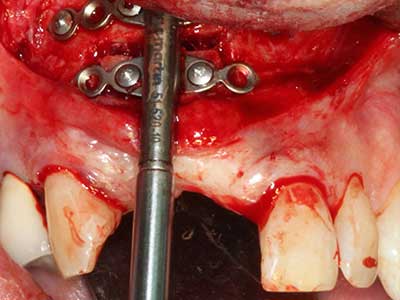

Fig. 28: During removal of metal, the basal chin regions are separated with the Piezomed while retaining the lingual blood supply.

Fig. 29: Forward displacement of the chin by 5 mm and fixation with two osteosynthesis plates (KLS Martin). The two mental nerves can be detected in the marginal region.